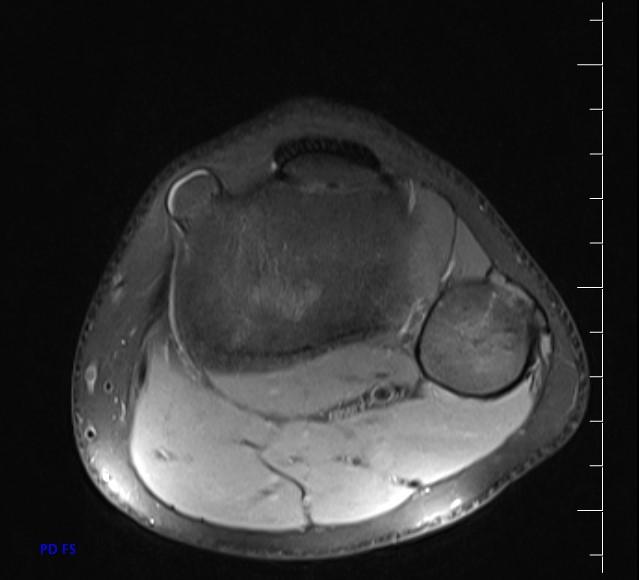

*13-year-old boy with mass on the proximal tibia.

Answer: Osteochondroma

MR images show osteochondroma on the proximal tibia.

MRI is the best imaging procedure to evaluate cartilage thickness, presence of edema in bone or adjacent soft tissues, and visualizing neurovascular structures in the vicinity.

The cartilage cap appears the same as cartilage elsewhere, with intermediate to low signal on T1WI and high signal on T2WI. The cartilage cap of over 1.5 cm in thickness is suspicious for malignant degeneration. The cartilaginous cap itself should not enhance.